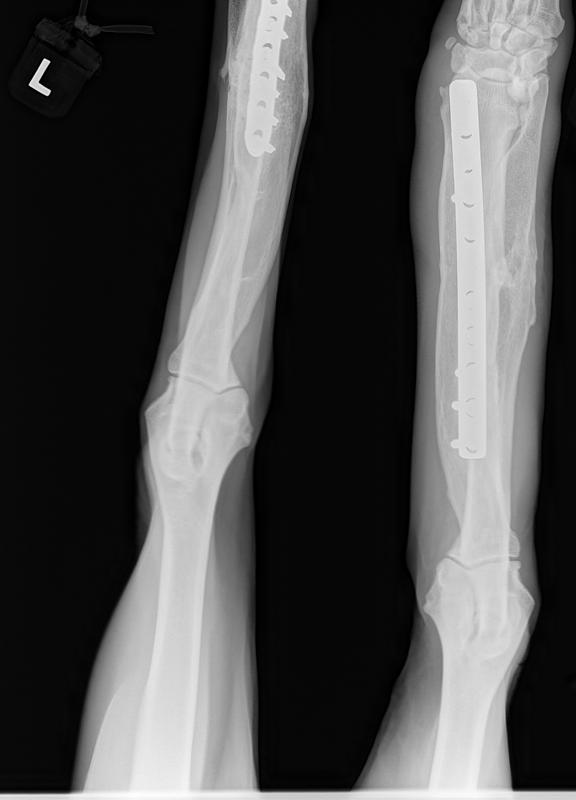

He had to have a total of 4 leg surgeries on his front legs and he is now a happy, healthy, super affectionate, butt nipping if you ignore him and really life loving boy!

His surgery to remove the implant on his left front leg after a sudden rejection/infection with the plate screws was on September 24th. This is his fourth leg surgery. He had two surgeries on his front legs which were deformed when he first arrived to BHRR and then now he has had to have two more surgeries due to reacting to the Implants.

Surgery started late yet all is done and The Mavie, our true Iron Man has his ‘new’ leg!

Everything went great for BHRR’s Maverick. His temp is low yet rising and the initial thought was to send him home on IV fluids yet, the end decision was to take him off as he is doing very well.

BHRR’s Mavie is having that front left leg implant removed. He developed a sudden infection and rejection of the plate/screws.

He has his surgery scheduled to remove that left front leg implant on Tuesday November 24th with his wonderful ortho specialist. He had a sudden rejection/infection to that left implant recently and now that the Baytril(almost $600 for 16 days worth of treatment) has worked its magic on the infection, he is ‘good to go’ for surgery!